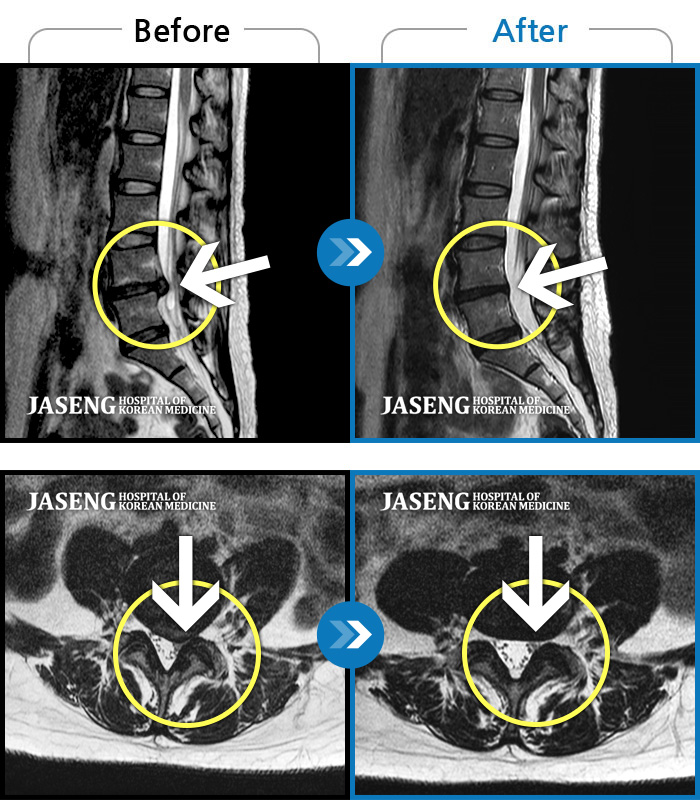

• 허리디스크